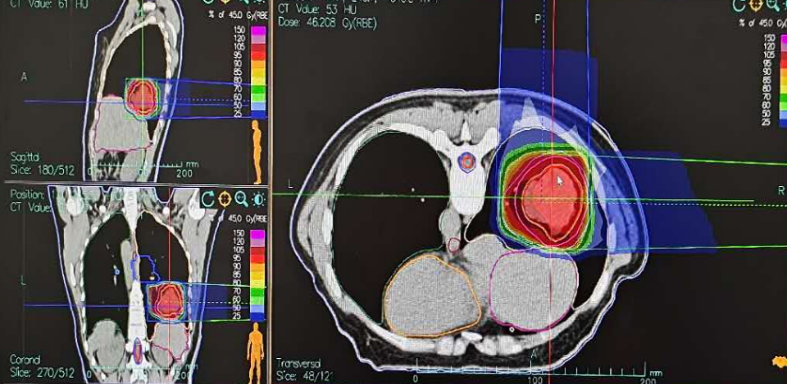

2.Treatment Plan:

• Right Choroidal Tumor: GTV: Right choroidal tumor; PGTV: GTV with 2 mm margin. Dose: 70 Gy(RBE)/5 fractions.

• Lung Tumor: GTV: Right lung lesion; CTV: GTV with 8 mm margin; PTV: GTV and CTV with 5 mm margin. Dose: CTV: 45 Gy(RBE)/15 fractions; GTV boost: 27 Gy(RBE)/3 fractions; Total dose: 72 Gy(RBE)/15 fractions.

Figure 2: Radiotherapy Target Volume for Right Choroidal Tumor GTV: Right choroidal tumor; PGTV: GTV with a 2 mm margin. Dose: 70 Gy(RBE)/5 fractions

Figure 3: Radiotherapy for Right Lung Lesion CTV: 45 Gy(RBE)/15 fractions; Tumor Boost: 27 Gy(RBE)/3 fractions; Total Dose: 72 Gy(RBE)/15 fractions